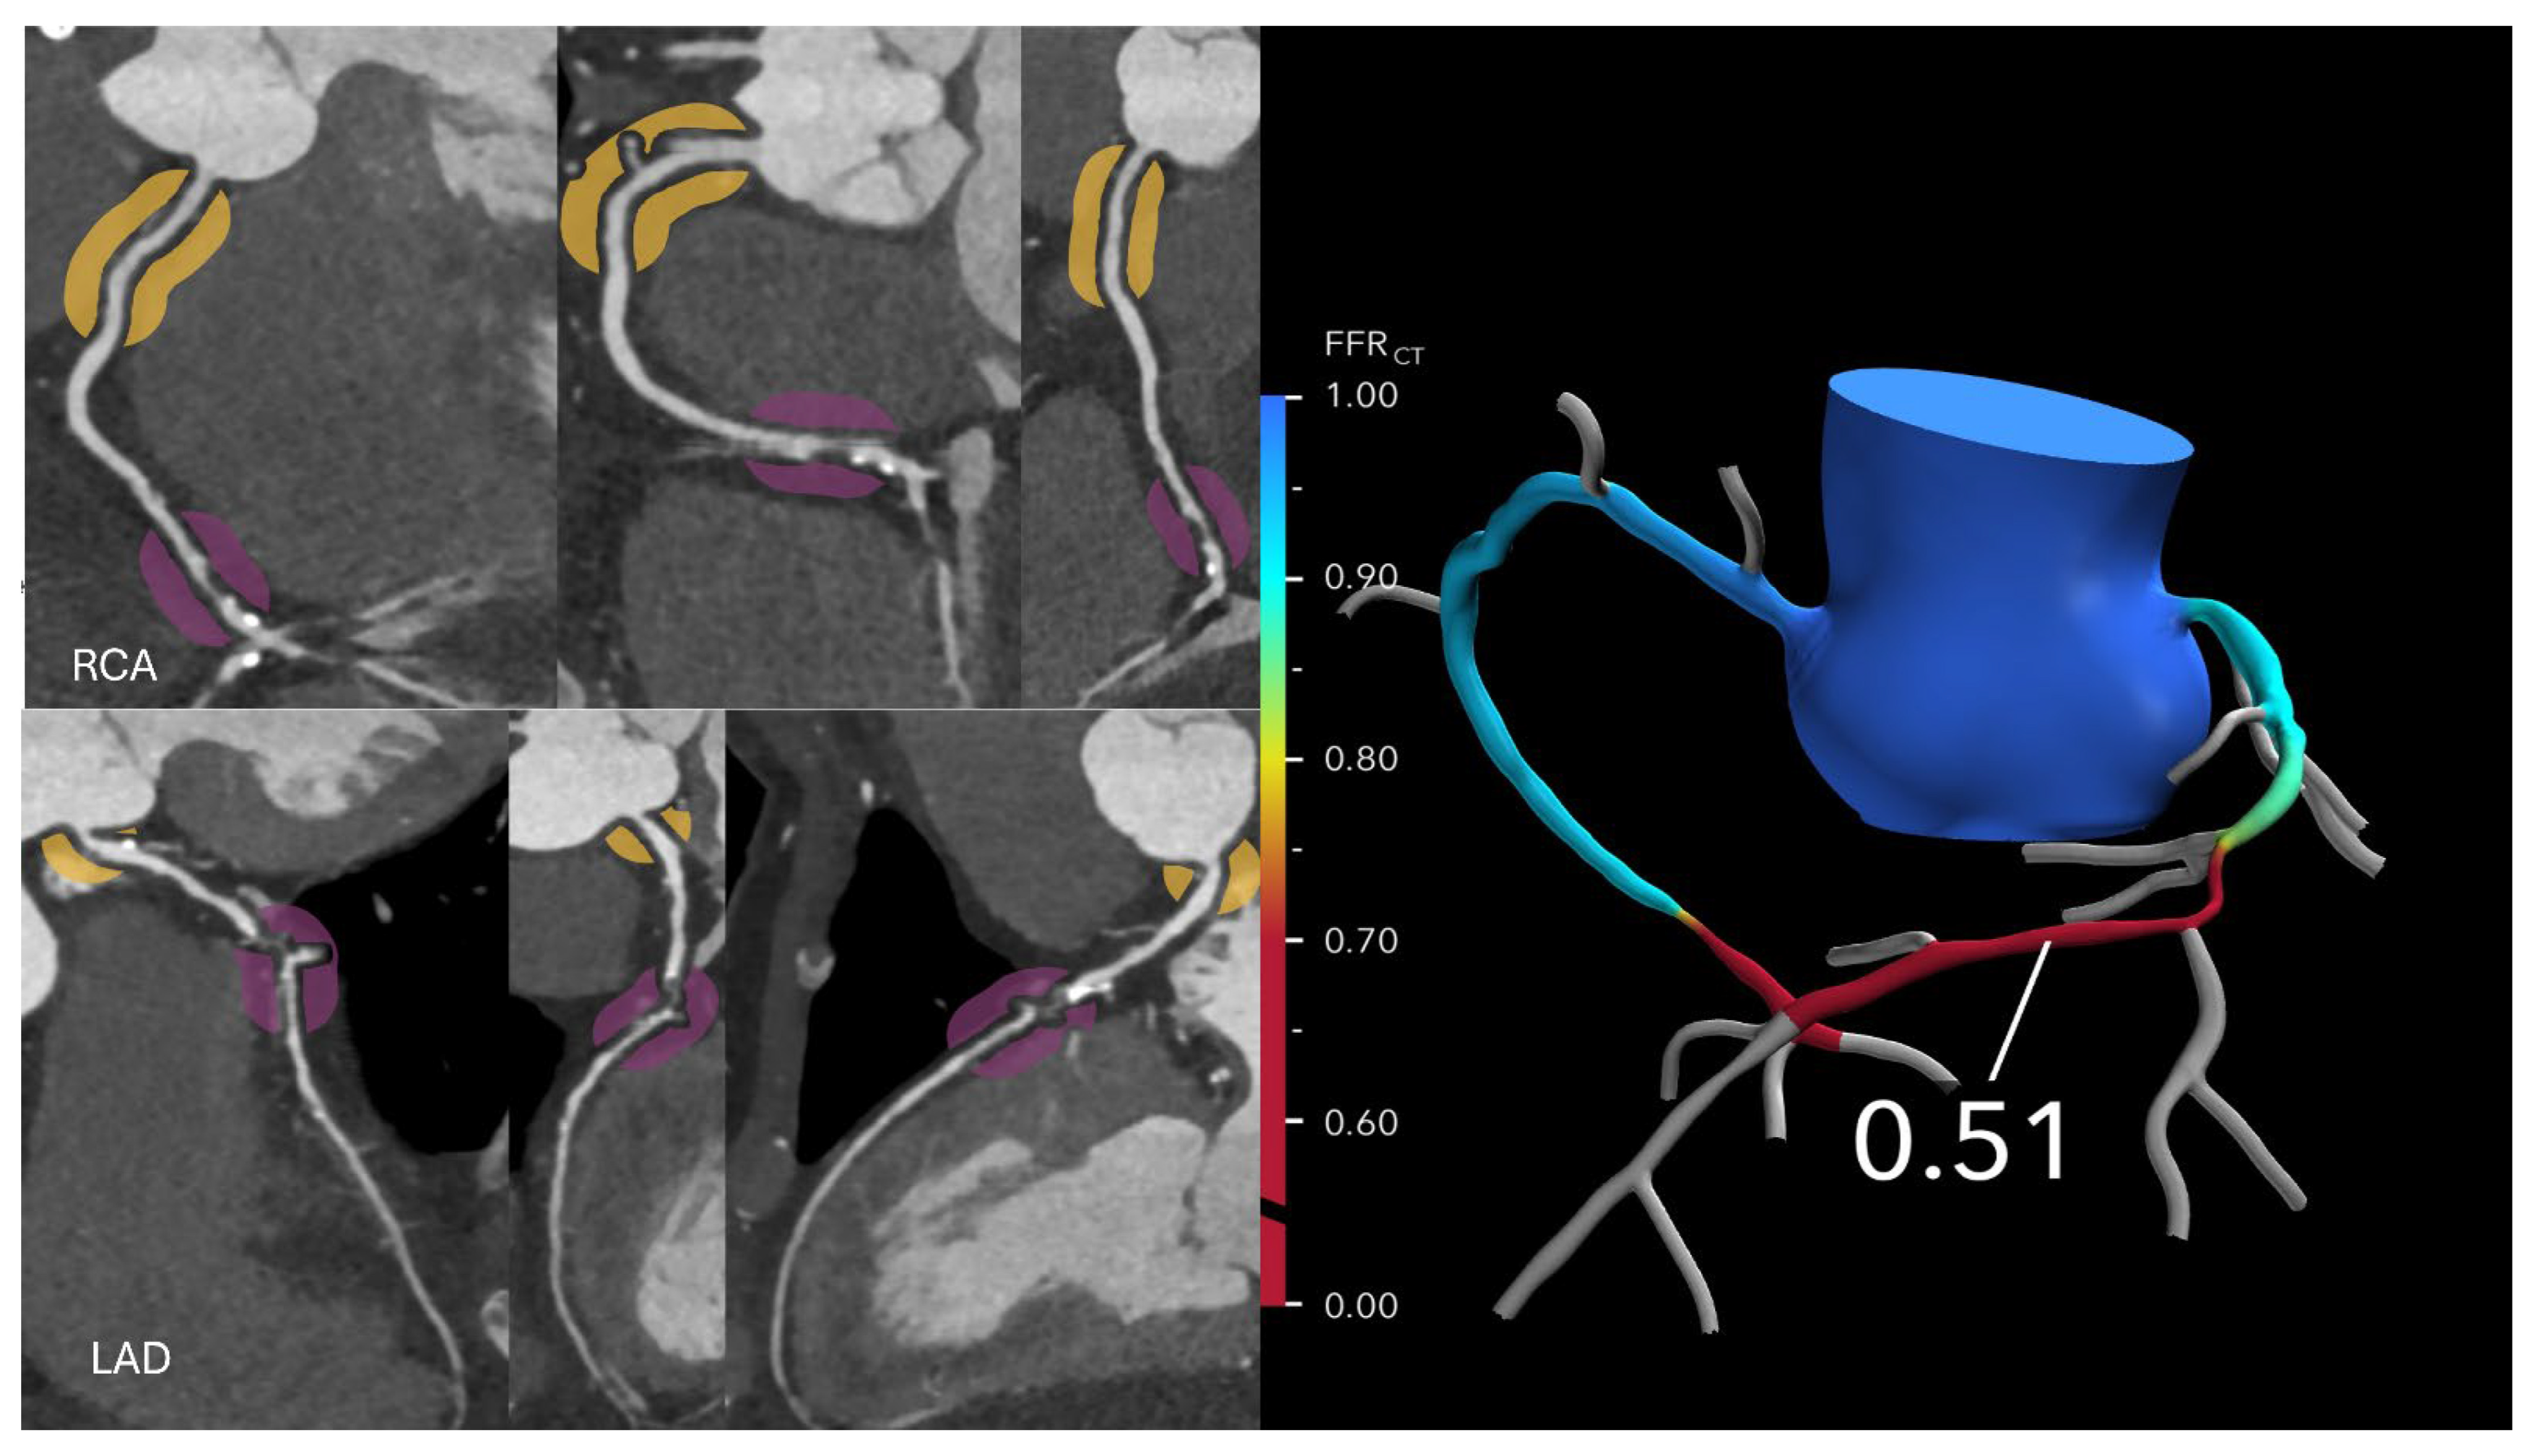

Figure 4. Anomalous aortic origin of the left coronary artery. (Left): Curved multiplanar reformatted coronary CT angiography (CTA) images in a 65-year-old male patient demonstrate severe stenosis at the ostium of the right coronary artery (RCA) and moderate stenosis at the ostium of the left anterior descending (LAD) artery, both originating from the right coronary cusp. (Right): Corresponding fractional flow reserve computed tomography (FFR-CT) images show a value of 0.50 at 2 cm distal to the RCA ostial lesion, indicating significantly reduced flow. The mid LAD displays a value of 0.78, and the distal LAD shows a value of 0.71, suggesting a high likelihood of hemodynamic significance. Based on these findings, the patient proceeded to invasive coronary angiography and subsequent intervention for both lesions. Reprinted with permission under open access from Kasaeian et al. [6].

Kasaeian et al. reviewed the clinical applications of FFR-CT in coronary artery disease [6]. FFR-CT has been increasingly reported in the literature to yield improved accuracy in guiding patient management compared to standard coronary CT angiography (CTA). Real-world evidence of using FFR-CT in clinical practice has been validated by a number of multicenter trials proving that FFR-CT serves as a gatekeeper to invasive coronary angiography by reducing a significant number of unnecessary invasive procedures (Figure 2 and Figure 3). FFR-CT is associated with significantly lower all-cause mortality, so it can guide confidential clinical decision-making. Judicious use of FFR-CT to guide coronary CTA interpretation was discussed alongside distal-to-lesion FFR-CT measurement, showing improved concordance with invasive FFR, hence further enhancing diagnostic precision. In this study, the limitations of FFR-CT are highlighted, along with the impact of high-quality coronary CTA image acquisition and coronary calcium scores on FFR-CT performance. Future potential applications of FFR-CT, such as its implementation in the evaluation of coronary artery anomalies (Figure 4) and plaque characterization, are also reviewed. These authors also reviewed the role of FFR-CT as a reliable tool to plan percutaneous coronary intervention (PCI) and identify suitable patients undergoing coronary artery bypass grafting. Finally, they summarized the role of FFR-CT combined with risk stratification as a gatekeeper to the catheterization lab to reduce unnecessary invasive procedures without comprising clinical outcomes.